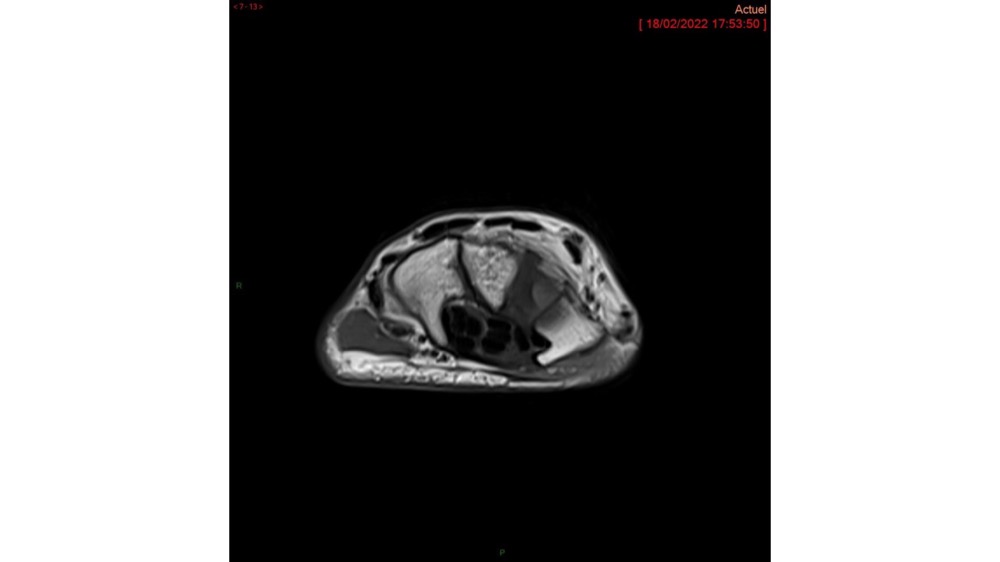

Hussein / Miquel 23/03/2022